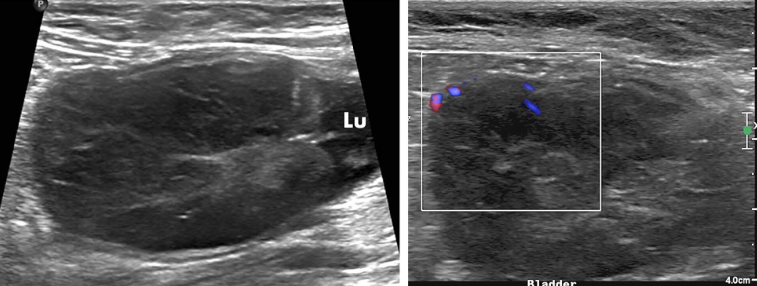

고양이 방광벽에서 생긴 평활근종의 초음파 소견

고양이에서 보기 드문 육종이 방광에 생겼을때 보일 수 있는 초음파 소견을 소개하는 논문.